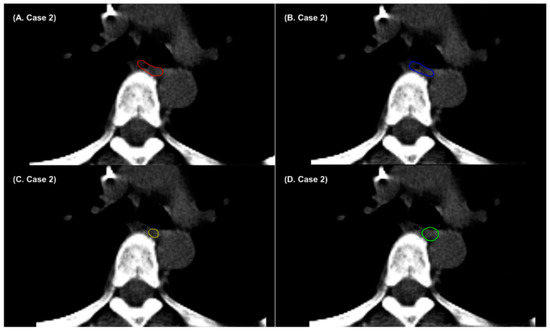

3. Results